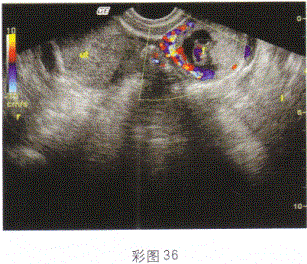

女性,28岁,停经45天,阴道不规则出血1周;尿妊娠试验阳性;结合超声图像(彩图36),最可能的诊断是

- B.异位妊娠

宫腔内未见明显孕囊回声,于左侧附件区可见囊实混合性回声光团,边界欠清晰。结合患者症状及妊娠试验即应考虑为异位妊娠。